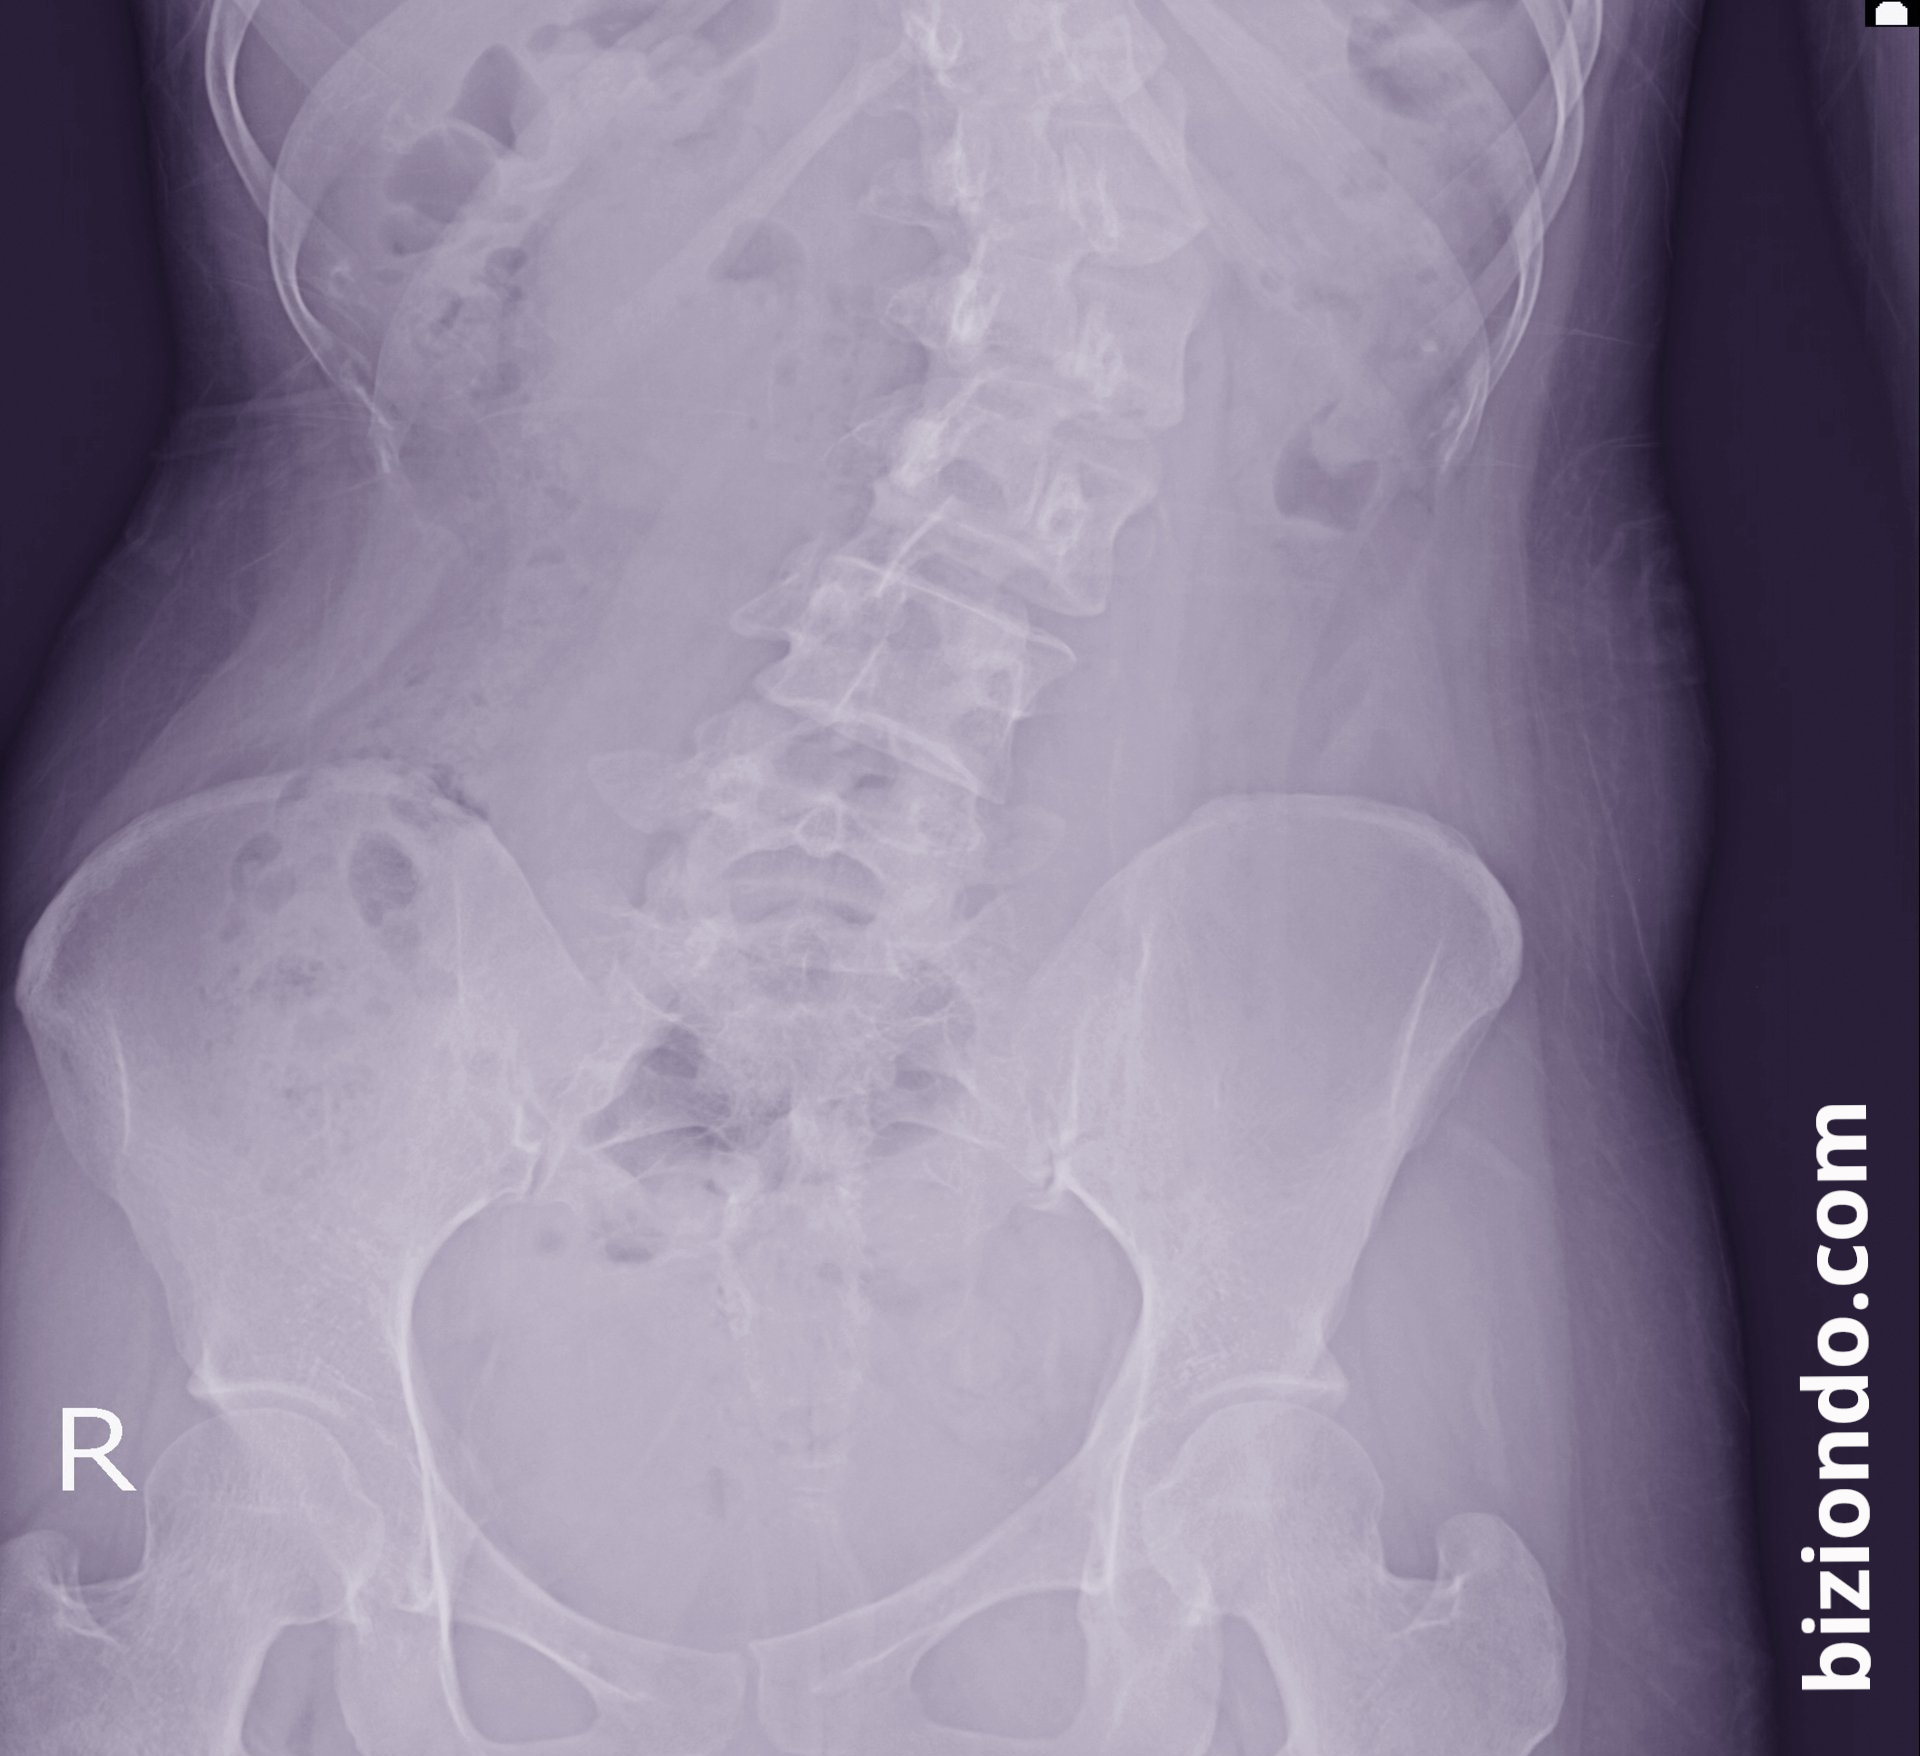

Degenerative lumbar scoliosis, also known as adult scoliosis, refers to an abnormal curvature of the spine that develops in adulthood due to natural wear and tear on the spinal discs and joints. This condition is different from idiopathic scoliosis, which usually appears in adolescence and whose exact cause is unknown.

To diagnose degenerative lumbar scoliosis, doctors usually perform a physical exam followed by imaging tests, such as X-rays, MRIs, or CT scans.